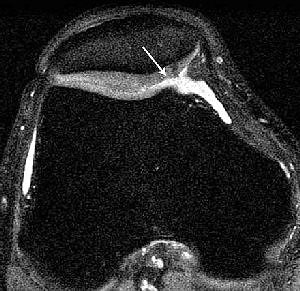

| Knee images in a 29-year-old man with knee pain. Axial proton-density image (TR/TE, 5,000/14; matrix, 512 x 384; slice thickness, 2 mm) acquired at 1.5-tesla shows fraying of lateral patella cartilage (arrow). Knee images in a 29-year-old man with knee pain. Axial proton-density image acquired at 3-tesla with identical parameters shows improved signal-to-noise ratio (SNR). Improved depiction of fraying of lateral patella cartilage (arrow) is seen at 3-tesla. Overall SNR at 3-tesla allows imaging at higher resolution. Gold GE, Suh B, Sawyer-Glover A, Beaulieu B, "Musculoskeletal MRI at 3.0 T: Initial Clinical Experience" (AJR 2004; 183:1479-1486). |